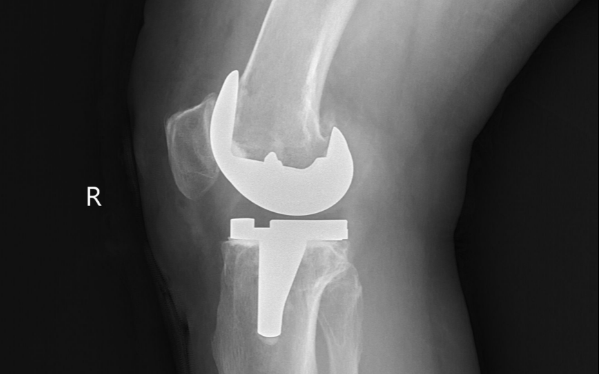

一般在骨折復(fù)位內(nèi)固定、關(guān)節(jié)置換、脊柱手術(shù)等各類骨科手術(shù)后,及早開展康復(fù)是非常必要的。只有進(jìn)行針對(duì)性、循序漸進(jìn)的康復(fù),才能逐漸解除運(yùn)動(dòng)受限,恢復(fù)肢體功能。

目前很多骨科患者做完手術(shù)后不知道康復(fù),認(rèn)為手術(shù)做完就萬(wàn)事大吉,回到家好好休養(yǎng)就可以,往往錯(cuò)過(guò)了康復(fù)最佳的時(shí)間,結(jié)果造成肌肉肌腱攣縮、關(guān)節(jié)僵硬,導(dǎo)致部分功能喪失。

骨科術(shù)后康復(fù)最早可在術(shù)后當(dāng)天進(jìn)行,術(shù)后4-6周為黃金康復(fù)期,術(shù)后三個(gè)月內(nèi)仍是骨科康復(fù)的最佳時(shí)段。